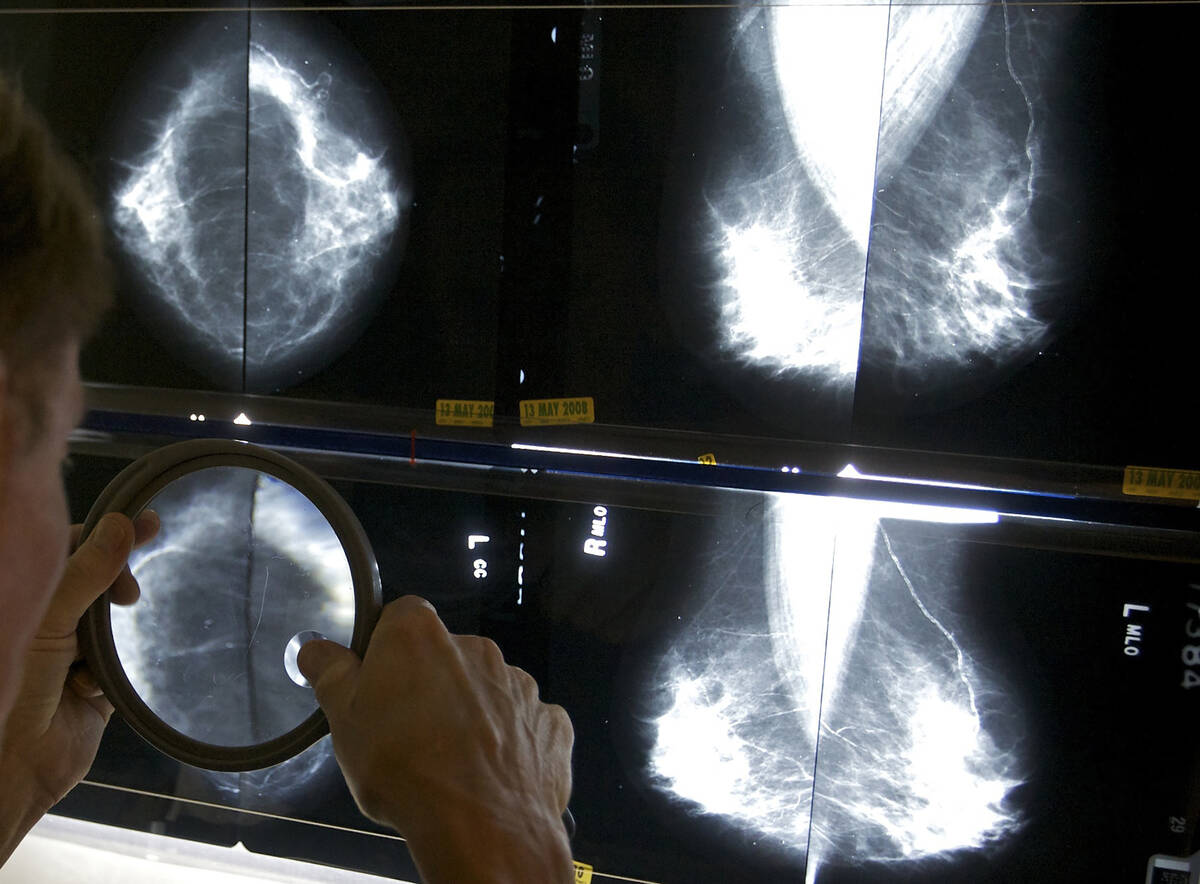

According to Salamat, the general recommendation for women of average risk is to begin annual mammograms — preferably the 3D type — at age 40. For women with a family history of breast cancer, screenings will probably begin earlier.

“I’d recommend all women be screened annually over the age of 40,” Christensen says, although modifications to that general guideline may be merited based on family history and personal circumstances.

For example, in the case of a woman who has a first-degree relative with breast cancer, screenings probably would “start 10 years before the first-degree relative was diagnosed,” she says.